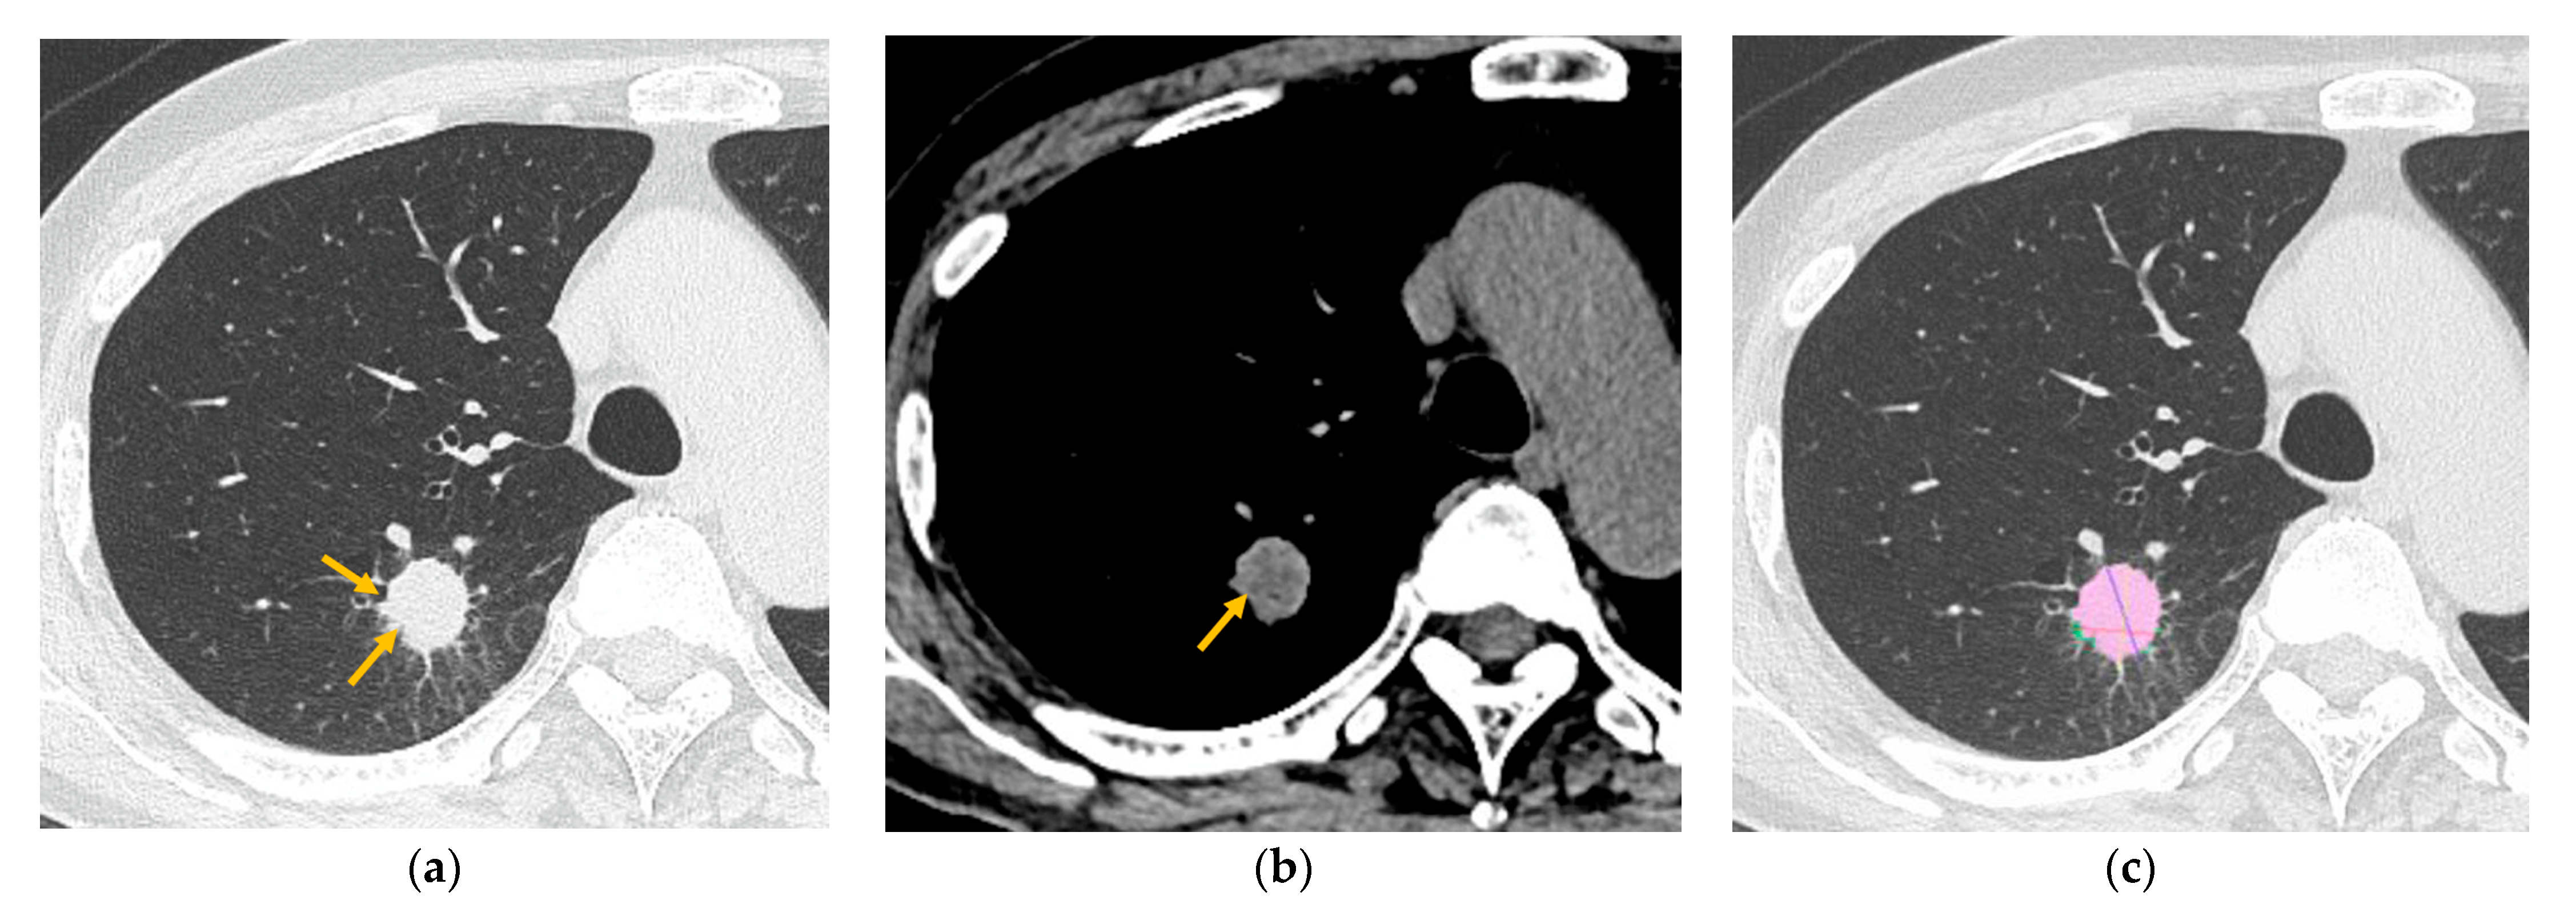

2.3. CT Analysis